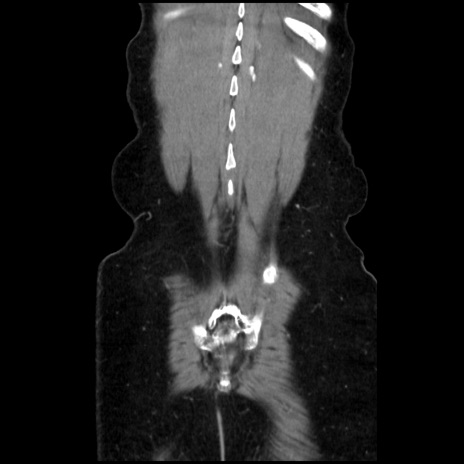

症例32(冠状断像)

【症例】40歳代 女性

【主訴】上腹部痛、嘔気・嘔吐

【現病歴】約9時間前頃から急に上腹部痛、嘔気、嘔吐が出現。改善しないため救急要請。

【既往歴】子宮頚癌(広汎子宮全摘術、放射線療法)、腸閉塞

【身体所見】腹部:平坦、軟、腸雑音亢進、上腹部を中心に腹部全体に圧痛あり。

【データ】WBC 8400、CRP 0.03

矢状断像